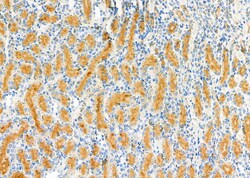

| Applications | Immunohistochemistry (Paraffin), Western Blot, Immunocytochemistry |